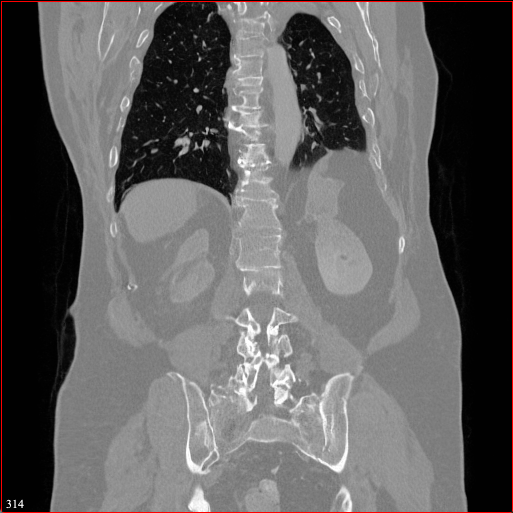

Figure 2: Qualitative comparison across axial (top row), sagittal (middle row), and coronal (bottom row) views. Columns correspond to different methods. MAISI-DDPM and MAISI-v2 in this figure are unconditional synthesis which do not use ControlNet or segmentation maps.

Qualitative Evaluation:

Figure 2 presents representative slices from the axial, sagittal, and coronal planes. GenerateCT (Hamamci et al. 2024) is a 2D model, so it lacks inter-slice consistency, leading to poor image quality in the sagittal and coronal views. MedSyn (Xu et al. 2024) produces noticeably blurry results with mosaic-like artifacts, such as region inside the red box. HA-GAN (Sun et al. 2022) generates visually sharp images but with mosaic-like artifacts, such as region inside the red box. Also, its voxel spacing is not available, which limits its applicability in real-world medical imaging tasks. Moreover, all three methods are restricted to synthesizing small anatomical regions. In contrast, both MAISI and MAISI-v2 are capable of generating high-quality 3D volumes that span larger body regions while preserving fine anatomical details and realistic structure.